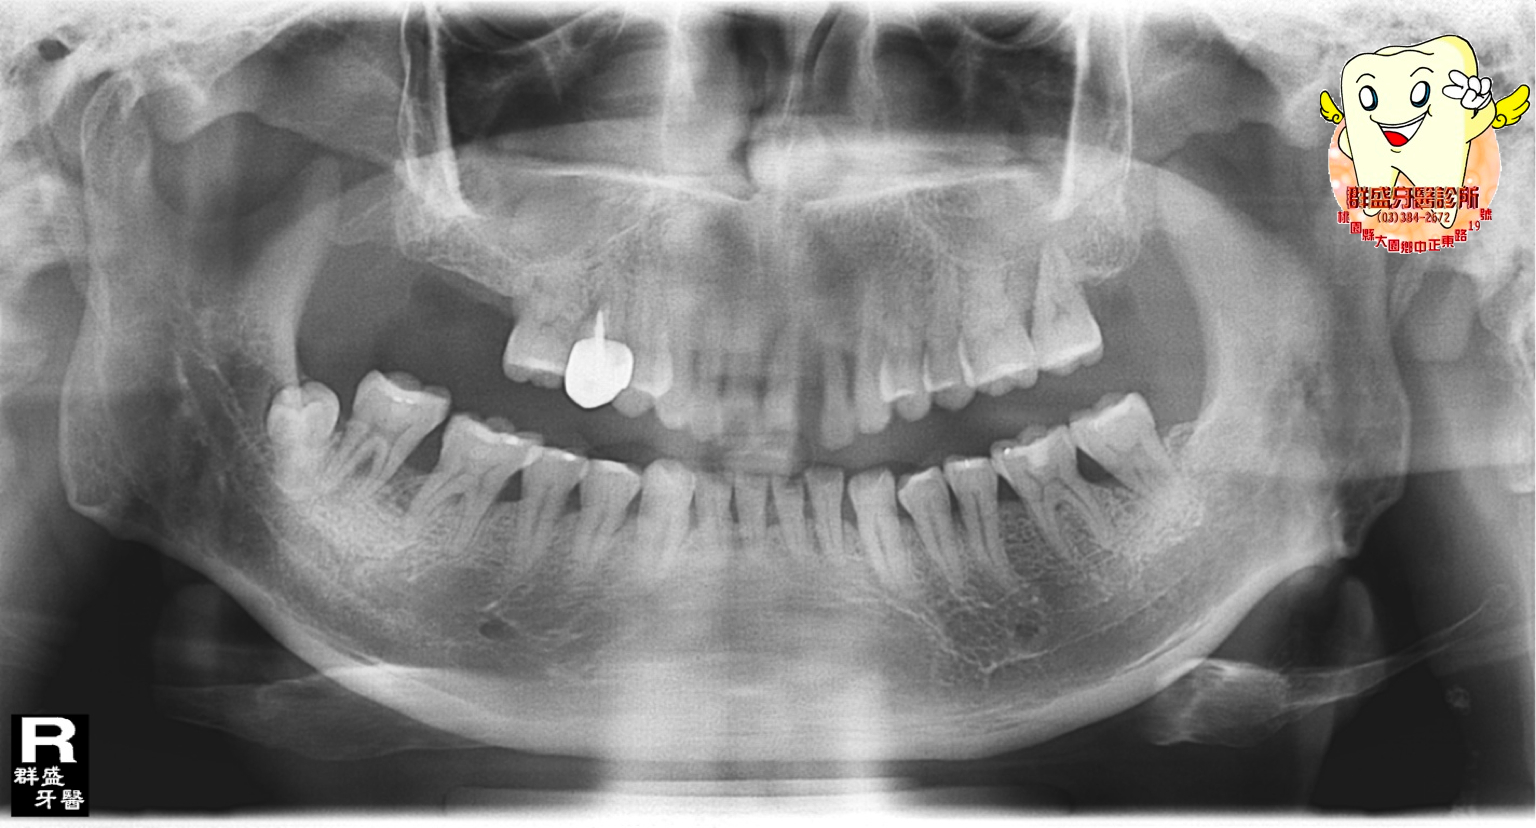

在年輕的時候一次不小心咬到異物造成前牙位移,慢慢的形成了嚴重的牙周病,因為牙根周圍的骨頭已經幾乎全部壞光,

所以當這些牙齒拔除後骨頭條件已是不足以提植牙的不良地基,我又不想將左右的好牙磨掉,傳統的假牙牙橋必須要將左右好的牙齒磨小,常造成牙齒壽命的減短,所幸歐醫師為我施行了“骨引導再生手術”,恢復了我的齒槽骨,並在半年後植入人工牙根,不但解決了我牙齒缺失的問題,一併解決了我前牙位移的外觀。